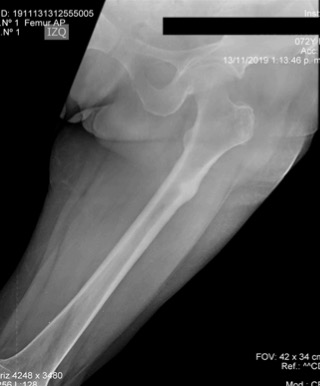

Sin embargo, antes de ser revalorada con estos resultados de imágenes la paciente presenta un trauma de baja energía a nivel del muslo izquierdo por una caída de su altura, con posterior dolor, deformidad en el muslo y limitación para la marcha. Se toman nuevas radiografías que muestran una fractura subtrocantérica de fémur izquierdo completa, transversa y desplazada, con un engrosamiento perióstico de la cortical lateral a este nivel, a nivel de la cortical medial un pico hacia distal, un hallazgo característico de las fracturas atípicas de fémur (Figura 4). Se realiza manejo quirúrgico con una reducción cerrada y fijación interna con un clavo endomedular anterógrado de fémur (Figura 5). La paciente inicia rehabilitación posterior al procedimiento, recuperando la marcha y la movilidad completa de cadera y rodilla. En los seguimientos ambulatorios, ante la presencia de una fractura atípica en una paciente con osteoporosis asociada al uso de antiresortivos, se decidió modificar el tratamiento a teriparatide.

Imágenes de fémur izquierdo (B) donde se evidencia una fractura atípica de fémur izquierdo, una fractura subtrocantérica completa transversa sin conminución, con un pico medial y un engrosamiento localizado del periostio lateral documentado en estudios previos.

Figura 4: Imágenes de fémur izquierdo (B) donde se evidencia una fractura atípica de fémur izquierdo, una fractura subtrocantérica completa transversa sin conminución, con un pico medial y un engrosamiento localizado del periostio lateral documentado en estudios previos.